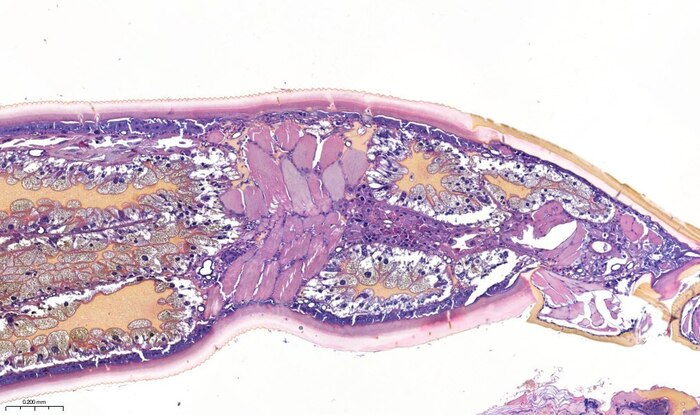

Угадайте опухоль, господа!

Ни за что не угадаете!

Дорогие коллеги, доброе утро.

Удивительно, но это второй такой случай в нашей практике.

Первый был довольно давно и тогда направительный диагноз звучал как «бустрорастущая меланома».

В этот раз обошлись папилломой грудной клетки.

В прошлый раз с такой «опухолью» столкнулся Станислав, в этот раз мне это прислал наш доктор – Д.К. Корнюшин, за что ему мои благодарности.

Да, коллеги – это клещ. Иксодовый. Может как-то еще сложнее называется – я не разбираюсь в них. Кто-то сказал, что это самка – не знаю половых признаков клещей, может и здесь вы правы.

По поводу радикальности метода удаления ничего сказать не могу. В оправдание ситуации могу предположить, что степень выраженности изменений в окружающих тканях подвигла на такой метод лечения. Впрочем, диагноз направления мог бы быть иным, учитывая макроскопическую картину.